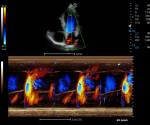

Lumi 4D enables the adjustment of light source angle to support real-time static stereo imaging of the fetus.